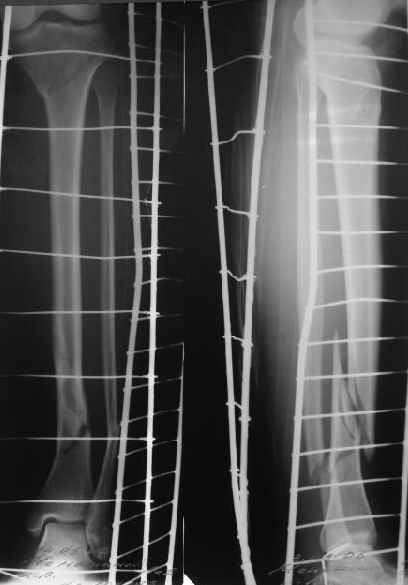

Направили к нам пациентку 35 лет с переломом дистального отдела костей голени.

У нас сделали снимок сзахватом обоих суставов - еще и проксимальный метафиз сломан. Чем бы у вас фиксировали такой перелом? Как его правильно закодировать по классификации АО?

Наверно, лучше всего по Илизарову.Что-то похожее я соперировал лет7-8 назад.Как кодировать по АО не знаю. А вообще зачем нужна кодировка по АО?

I don't know about the coding, but this looks like an ideal case for Ilizarov fixator.